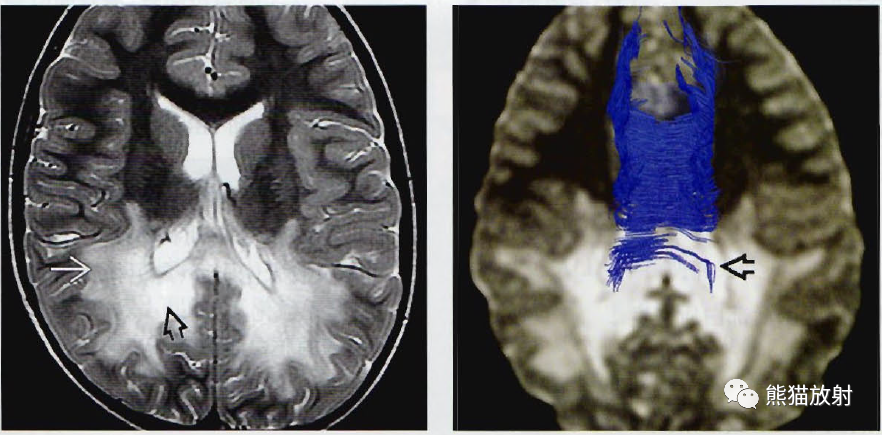

(左) 一位大脑完全受累的青春前期的男孩,轴位T2WI MR可分辨外层的活动性炎症(白箭)和最内层白质破坏的“彻底毁损”区(黑箭)。

(右) 另一位患CCALD的有临床症状的青春前期男孩,DTI序列的胼胝体轴位纤维束成像显示穿经胼胝体压部(箭)和胼胝体辐射线枕部的白质纤维束明显缺失。